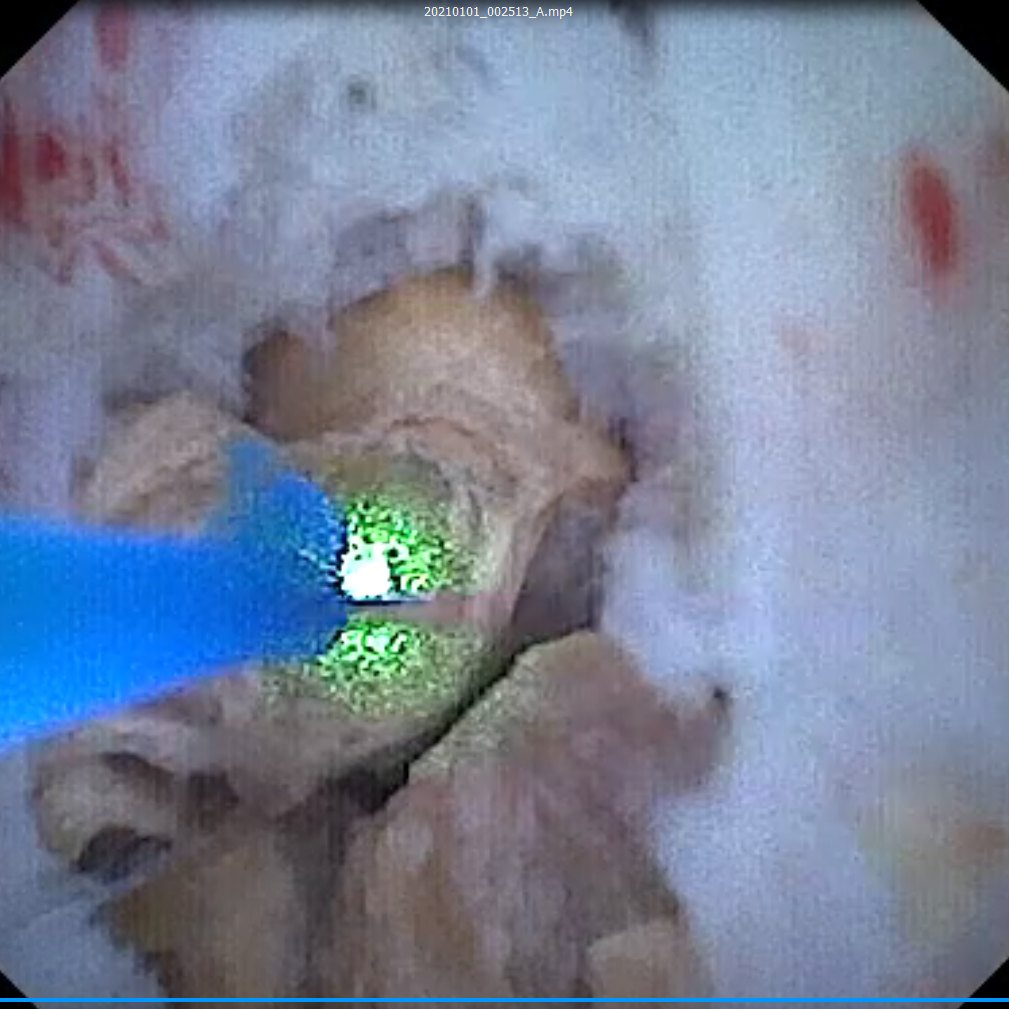

左侧输尿管结石碎石术顺利完成。术后一个月,张女士病情平稳,专家拟为其行经尿道软镜钬激光碎石取石术。虽然在术前CT中可明显看到结石,但在术中却未发现显露的结石。结石的位置一旦判断错并切开,将给患者带来严重的肾损伤。张鸿毅主任凭借多年临床经验调整镜头,看到肾下盏粘膜泛着淡黄色后确定地说到:“这里就是结石的位置!”果然,张主任用输尿管软镜钬激光将粘膜切开,大量的结石便顷刻涌出。

经过近一小时的钬激光碎石后,团队终于将结石完全击碎并取出。用同样的方法,专家团队也解决了张女士的右侧巨大肾髓质结石。术后,张女士恢复良好,已顺利出院。